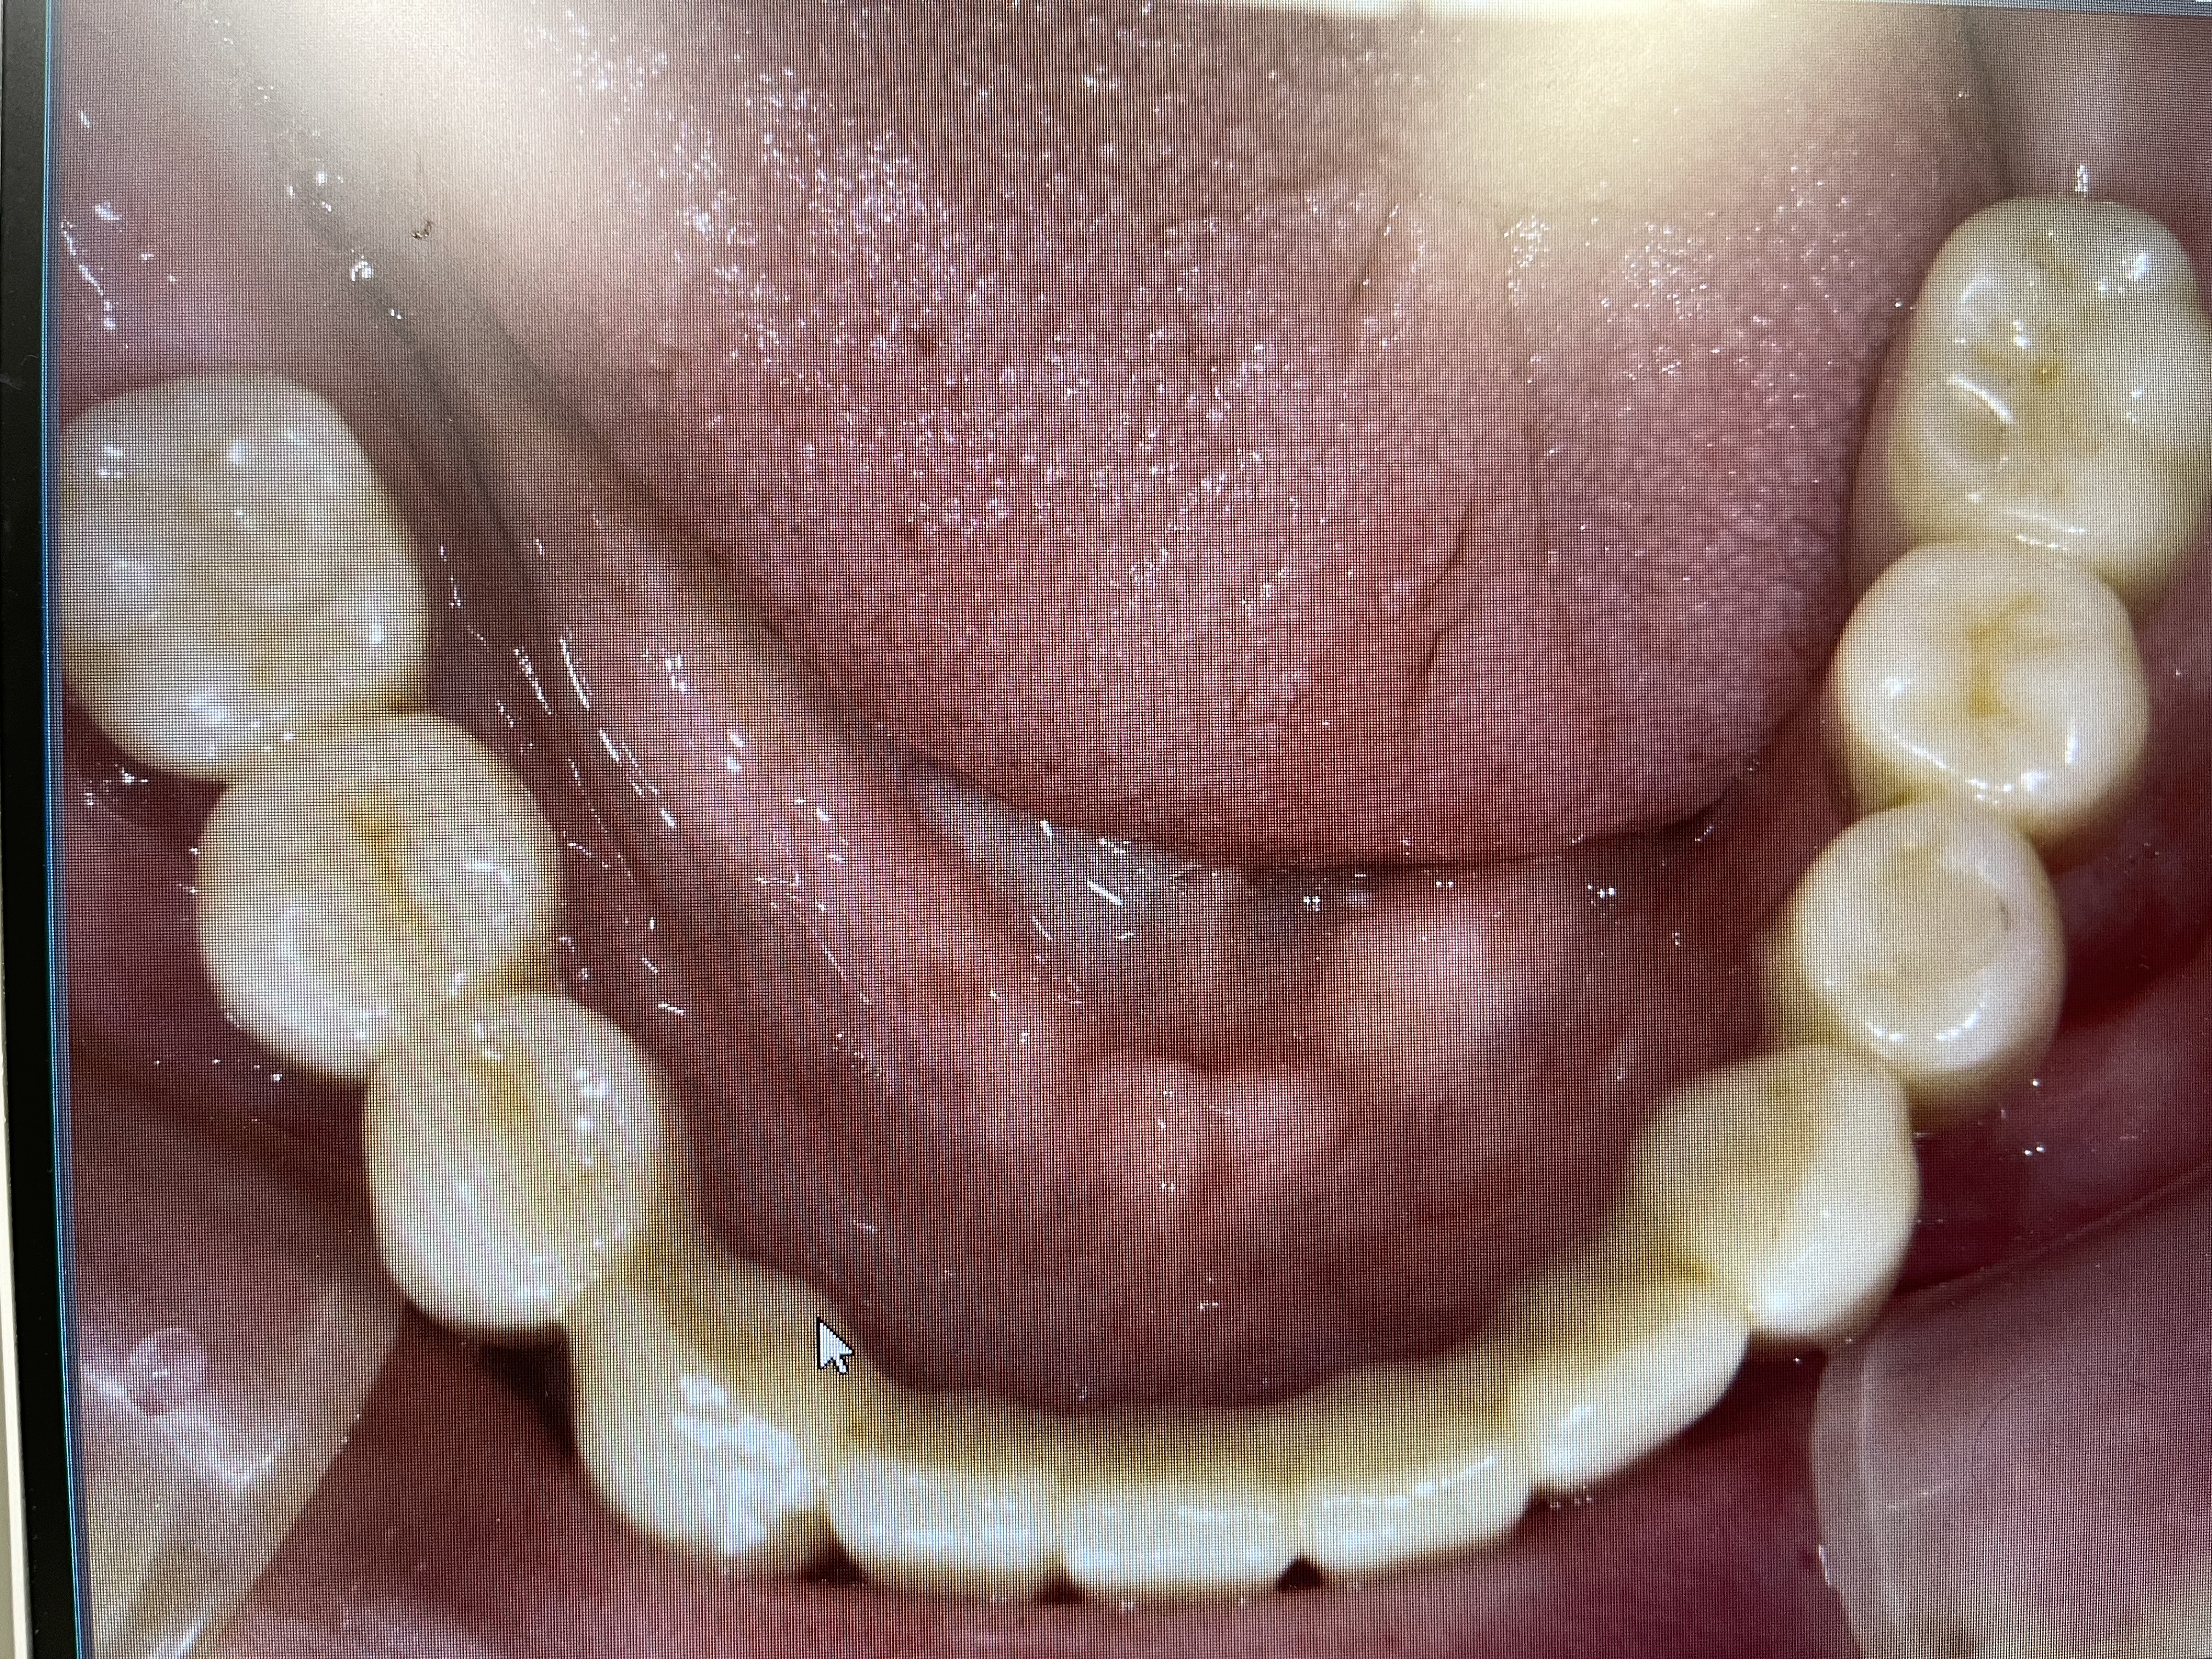

Title ” 総義歯の患者様のインプラント症例”

2024年暮れ、義歯(入れ歯)の痛みで

食事ができない患者様(75歳)が来院されました。

診察をしたところ、下顎の骨の痩せ方が著しく

義歯(入れ歯)が安定しにくいため

固定式のインプラントを提案しました。

固定式のインプラントをすることで、

上顎も外れない安定した総義歯になるということです。

下顎インプラントを4本埋入した状態

インプラントが4本埋入した下顎模型

下顎インプラント模型に仮歯が入っている状態

上部構造が入っている状態(下顎パノラマ写真)

下顎口腔内に最終補綴物(被せ物)が入っている状態

上顎総義歯&下顎インプラントブリッジが入っている状態(口腔内写真)